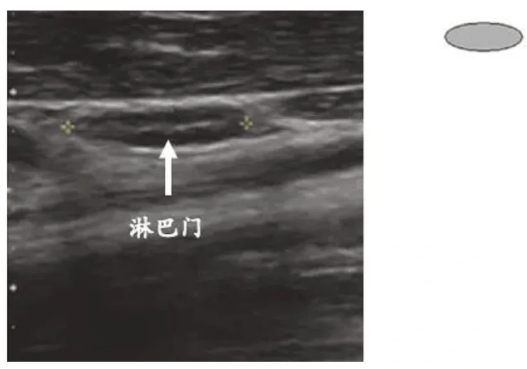

①正常淋巴结

正常淋巴结多呈椭圆形,长径通常<1cm,内部呈均匀低回声,可见清晰的淋巴门结构,即淋巴结中央的高回声区域,是血管、神经出入的通道,类似淋巴结的‘核心’。